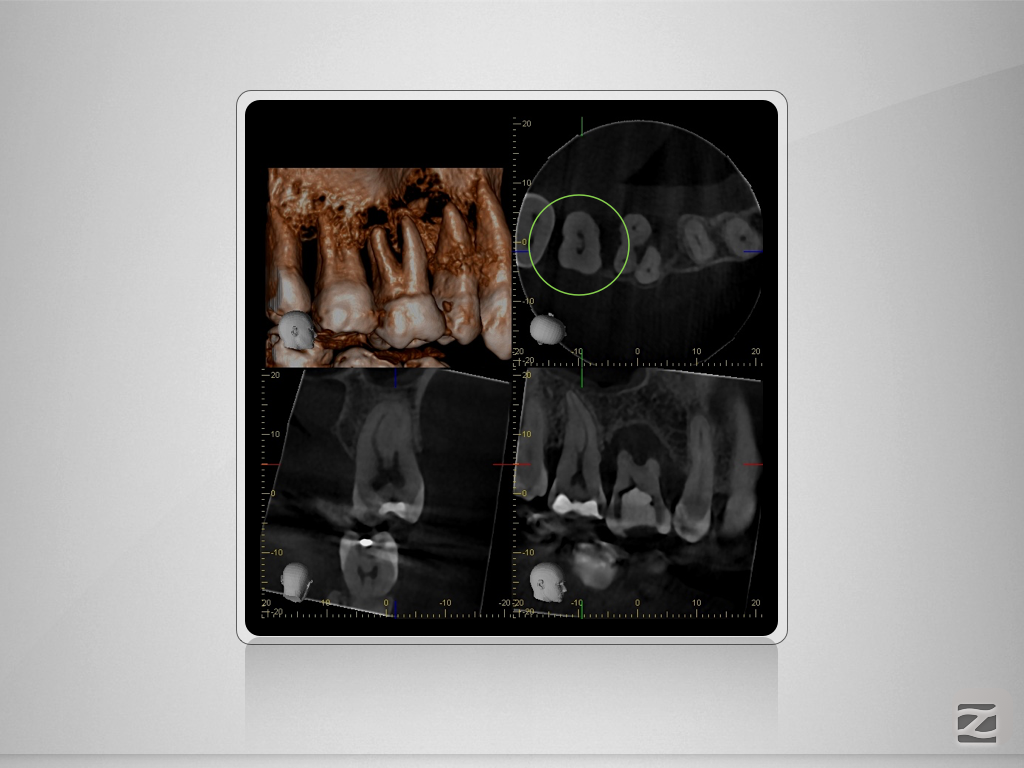

17D.005

Gewusst, wo’s lang geht.